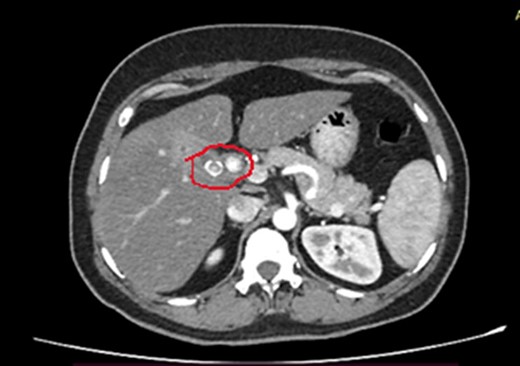

Laboratory investigations showed WBC 13.85 × 106, neutrophils 7.59, Hb 12.8 g/dl, platelet count 287 000 × 106, CRP 6.3, PT/INR 0.85, AST 75, ALT 53, ALP 88, and total bilirubin 12.0 mg/dl. Her ultrasound scan of the abdomen showed multiple common bile duct (CBD) calculi with intrahepatic and CBD dilatation with mild central cholangitis. Contrast-enhanced computed tomography (CECT) of the abdomen showed proximal CBD calculus with mild common hepatic and intra-hepatic duct dilation and gallstone with chronic cholecystitis (Fig. 1).